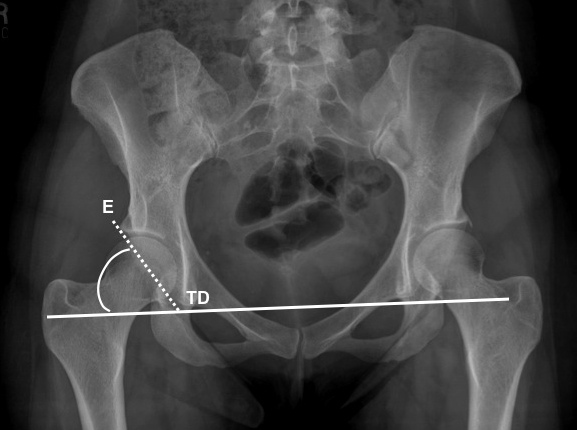

using the AP view of the hip, angle formed between lateral margin of acetabular roof or lateral sourcil (E) and inferior aspect of the pelvic "teardrop" (TD) and horizontal line between the inferior aspect of both pelvic "teardrops"

if > 38 degrees then acetabular dysplasia ( RID3737 )

how to draw the acetabular index or acetabular angle of sharp